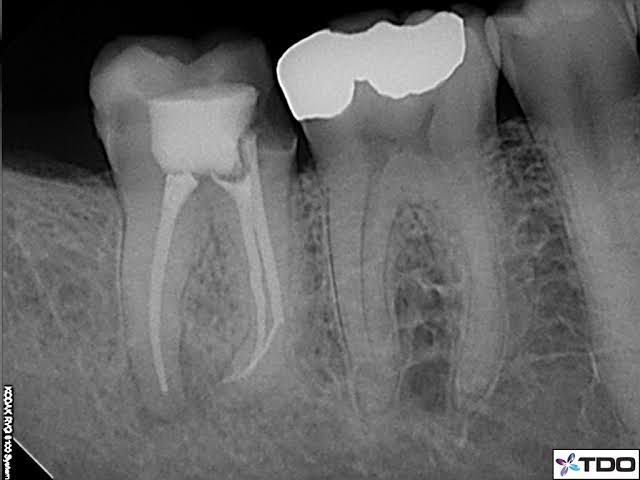

Instrument separation in the root canal is one of the most common procedural mistakes encountered during endodontic therapy. Instrument separation happens all the time, not just with students and general practitioners, but even with professional and seasoned clinicians, despite taking all precautions.